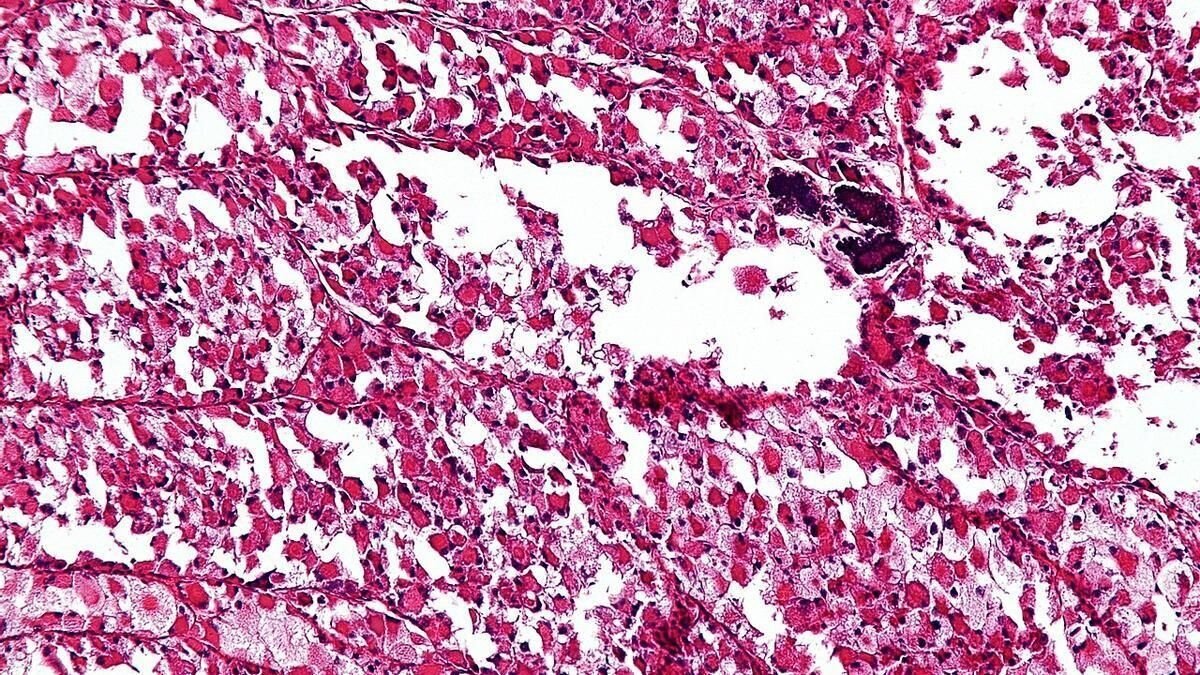

Sarcoma: el cáncer silencioso que puede pasar desapercibido durante años